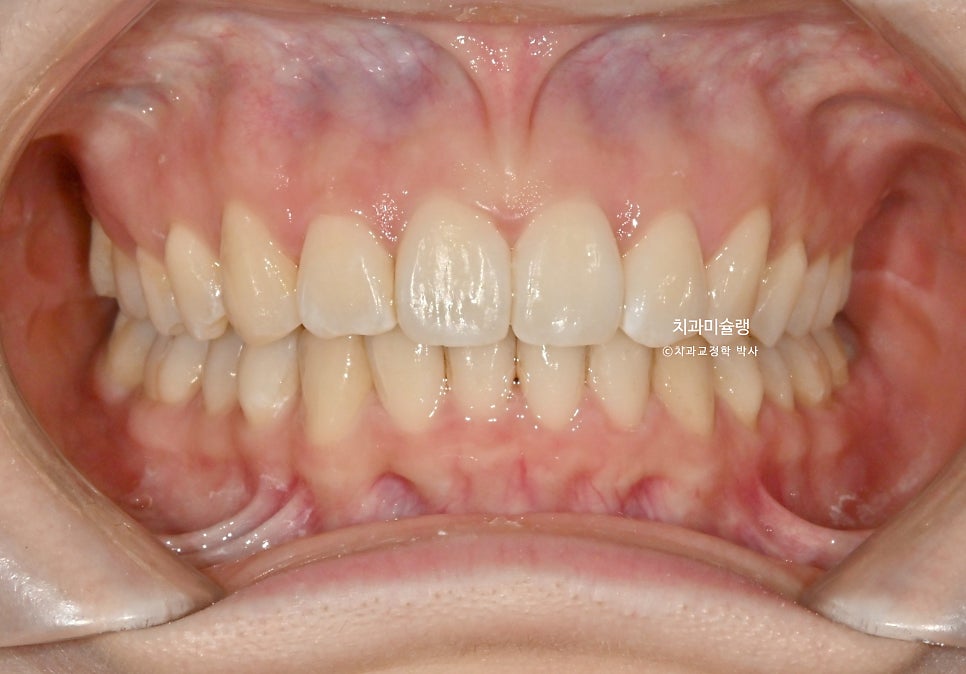

초진 상태 – 2025년 여름

2025년 여름, 앞니 부분교정을 하고싶어 온 환자분 입니다.

중심선 불일치가 보이며 아랫니가 거의 안보일 정도의 과개교합 입니다.

윗니중 가운데 앞니가 튀어나와있습니다.

최종 치료 결과 – 2026년 3월

어금니 교합은 물샐틈 없는 1급 교합관계를 보입니다.

작은어금니 회전까지 완벽 개선되었습니다.

안으로 쓰러져 있던 위 송곳니각도가 개선되었습니다.

들쑥날쑥했던 아래 앞니 잇몸 라인도 치아 높낮이가 조절되면서 자연스럽게 대칭이 맞아졌습니다.

중심선도 상당히 개선되었죠.